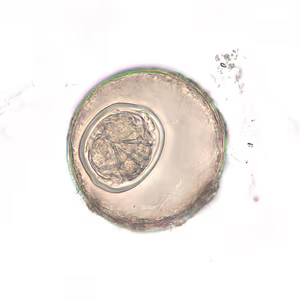

Hymenolepis diminuta eggs in wet mounts.